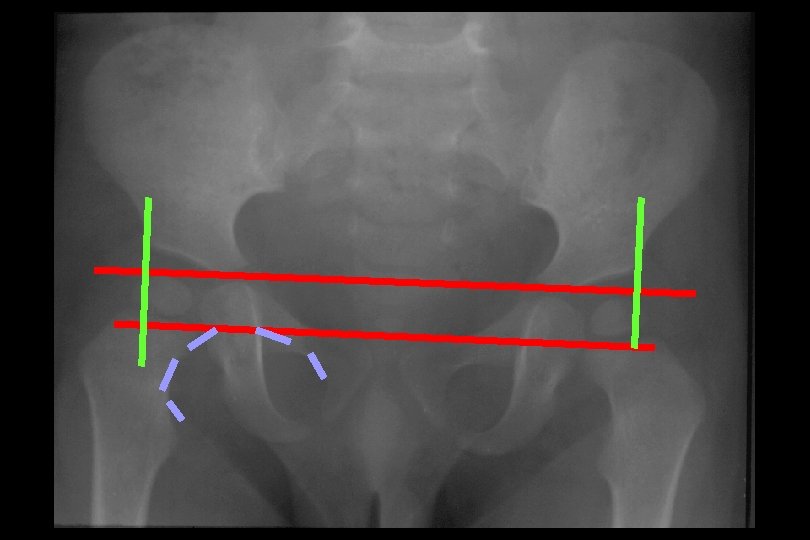

Radyolojik belirtiler • Erken • Geç Asetabular displazi Von Rosen II Shenton-Menard hattı Perkins kadranları

ASETABULAR AÇI ÖLÇÜLMESİ Asetabulum üst dış kenarı YD 27. 5 > 30 PATOLOJİK Y kıkırdağı Hilgenreiner çizgisi

VON ROSEN 1 HR Femur başı epifizi veya metafizin bir bölümü yer alır

VON ROSEN 2 45 ABD 20 DIŞ ROTASYON

SHENTON-MENARD HATTI KIRILMASI

PERKİNS KADRANLARI 3 4 2 1 Alt-iç: normal Alt-dış: sublukse Üst-dış: disloke